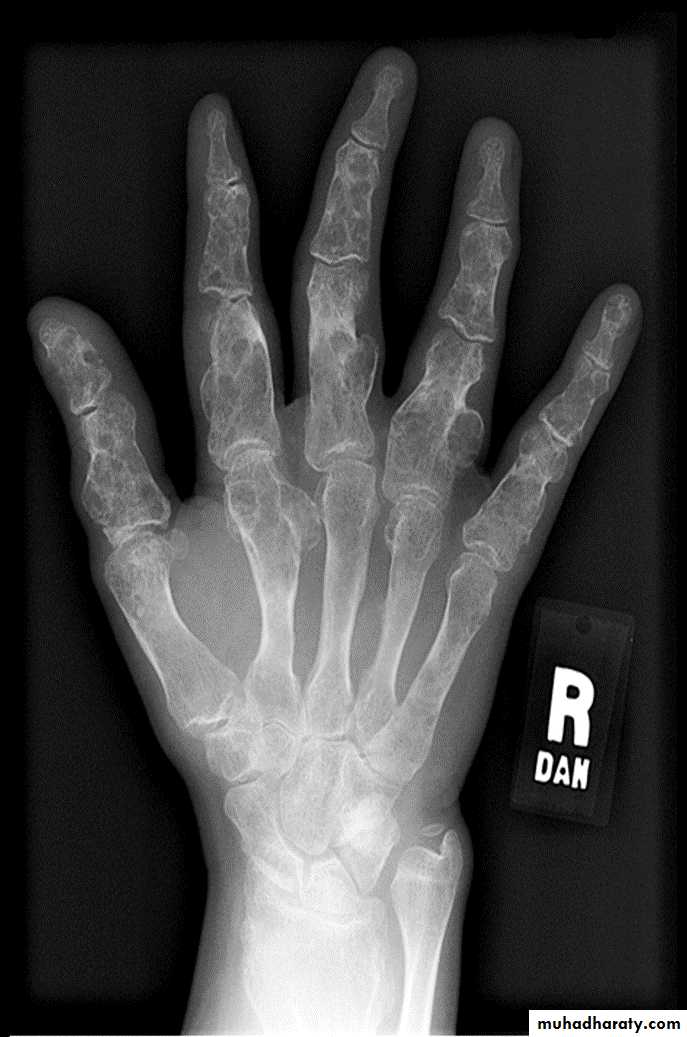

Multiple osteochondromasEnchondroma :

Multiple chondromas in the hand